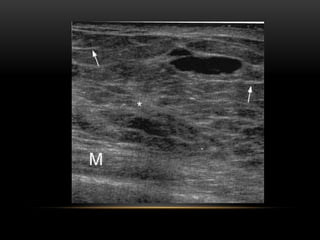

Forma

Ovalada

Redondeada

Irregular

Orientación

Paralela

No paralela

Márgenes

Circunscritos

No circunscritos

Límites de la lesión

Interfase abrupta

Halo ecogénico

Patrón ecogénico

Anecogénico

Hiperecogénico

Complejo

Hipoecogénico

Isoecogénico

Hallazgos acústicos

posteriores

Sin hallazgos

Refuerzo posterior

Sombra acústica

Mixto

Nódulos (ecografía)